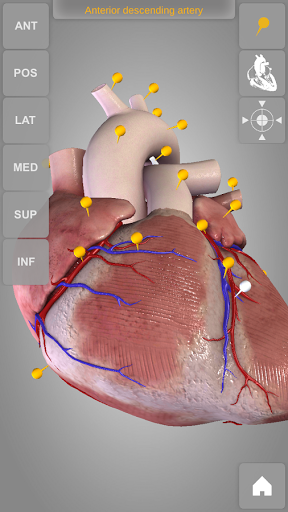

Heart 3D Atlas of Anatomy allows you to rotate a highly realistic 3D heart model as it was in your hands.

The human heart anatomical 3D model is revolvable in any direction giving a 360° view of the object.

User can choose external view or section view. Moreover, the names of specific anatomical areas can be shown touching the related pins (available in the full version only).

Heart app is part of 3D Atlas of Anatomy collection, a human anatomy reference atlas for tablet and smartphone devices. The 3D medical models in these apps are similar to classic real plastic models but with the great benefits to be always available on your portable devices when you need them and occupy no physical space.

These apps can be of great help for students of medicine or to anyone who needs to study human anatomy shape in detail and from any angle. Immediacy and simplicity together with high quality are distinctive features of the app.